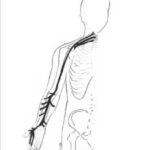

The Median Nerve Pathway

It all starts with pressure on the median nerve.

The median nerve starts in your neck, innervating your arm and hand. When it is pressed upon it will cause burning and numbness somewhere along its path, especially into your wrist, thumb and first two fingers.

The nerve passes under and through several arm muscles, through the carpal tunnel in your wrist, and finally a muscle of your thumb called the opponens pollicis muscle impinges on the nerve.

The nerve passes under and through several arm muscles, through the carpal tunnel in your wrist, and finally a muscle of your thumb called the opponens pollicis muscle impinges on the nerve.